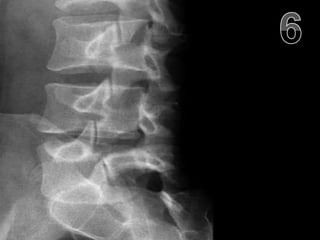

• Osteoporosis: The thinning of bone tissue

and loss of bone density over time.

• Which side of this picture show’s bone in

the later stages of osteoporosis?

• Answer! The picture on the right shows

serious bone thinning.